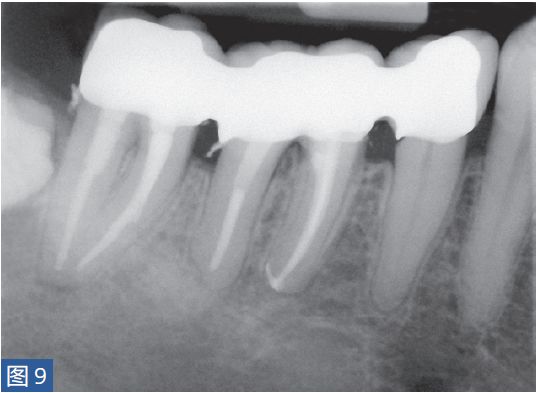

图8:47 牙齿AAA。术前X 线片。患者就诊时有发烧症状,且叩诊和触诊疼痛明显。

图9:47 牙齿AAA。根管治疗后。患者在其家庭牙医处做临时义齿修复12 个月后的检查。